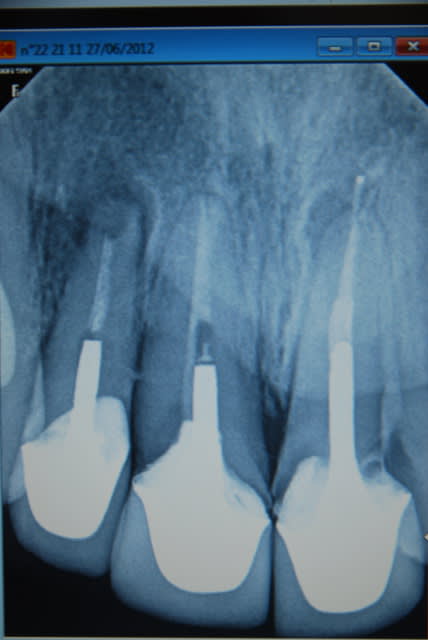

Je viens de revoir le patient et je peux vous apporter quelques précisions ainsi que des photos( désolé si la qualité n'est pas parfaite).

Patient de 45 ans, fumeur, motivé mais ne pouvant se payer d'implants.

Il a déjà vu plusieurs confrères qui lui ont proposé uniquement ( selon ses dires) une solution implantaire pour 12-11-21-22-23. Il souhaite du fixe...

En ce qui concerne la paro, la 12 est en mobilité stade 2, la 22 en stade 1 les autres étant non mobiles. Le sondage de 12 à 22 est de 3 mm, sauf en mésiale de 12 ( 6mm). La gencive est inflammatoire ( logique à la vue de l'inadaptation des couronnes, et des caries radiculaires).

Je pense lui proposer la solution du bridge avec 13,11,21,22, 24,25., même si la 13 est saine... Je prévoyais de reprendre l'endo de 22 mais la taille du tenon et sa longueur m'ont refroidi, peut être qu'une chir endo et obturation à rétro serait plus appropriées... Je prévois bien sur un surfaçage ainsi qu'un assainissement paro, une fois le bridge provisoire en place.

Tu as surtout un gros chantier paro à gérer. Et je ne pense pas que le tenon de la 22 soit si difficile à descendre, accessoirement l'endo de la 11 est aussi à revoir ( et là le tenon semble plus maousse ).